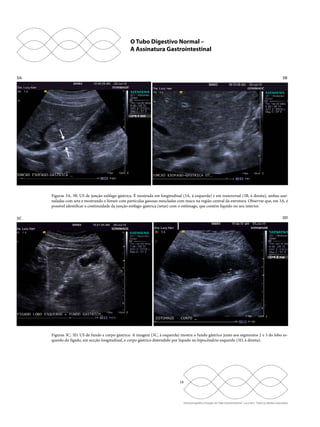

Figuras 3A, 3B. US de junção esôfago-gástrica. É mostrada em longitudinal (3A, à esquerda) e em transversal (3B, à direita), ambas assi-naladas

com seta e mostrando o lúmen com partículas gasosas mescladas com muco na região central da estrutura. Observar que, em 3A, é

possível identificar a continuidade da junção esôfago-gástrica (setas) com o estômago, que contém líquido no seu interior.

Figuras 3C, 3D. US de fundo e corpo gástrico. A imagem (3C, à esquerda) mostra o fundo gástrico junto aos segmentos 2 e 3 do lobo es-querdo

do fígado, em secção longitudinal, e corpo gástrico distendido por líquido no hipocôndrio esquerdo (3D, à direita).